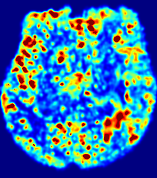

Slice #1Slice #2Slice #3Slice #4Slice #5Slice #6Dgtsuperscript𝐷gtD^{\text{gt}}Refer to captionRefer to captionRefer to captionRefer to captionRefer to captionRefer to caption(a)Refer to captionRefer to captionRefer to captionRefer to captionRefer to captionRefer to caption(b)Refer to captionRefer to captionRefer to captionRefer to captionRefer to captionRefer to caption(c)Refer to captionRefer to captionRefer to captionRefer to captionRefer to captionRefer to caption(d)Refer to captionRefer to captionRefer to captionRefer to captionRefer to captionRefer to caption(e)Refer to captionRefer to captionRefer to captionRefer to captionRefer to captionRefer to caption(f)Refer to captionRefer to captionRefer to captionRefer to captionRefer to captionRefer to captionRefer to caption000.060.060.060.120.120.120.180.180.180.240.240.240.300.300.30(mm2/s)𝑚superscript𝑚2𝑠(mm^{2}/s)

Figure 13: PIANO effectiveness and robustness testing: diffusion imaging via diffusion. Top row shows Dgtsuperscript𝐷gtD^{\text{gt}} used for simulating the ground truth pure diffusion. (a)-(f) refer to the results for D𝐷D estimated from the ground truth pure diffusion image time-series where Rician noise at levels 0%, 2%, 4%, 6%, 8%, 10% was added respectively.

Similarly, starting from the same initial condition C0superscript𝐶0C^{0} as in the ‘Advection Imaging’ experiment for each patient, we simulate concentration time-series {Cti(Ω)|i=0, 1,, 40}conditional-setsuperscript𝐶subscript𝑡𝑖Ω𝑖0140\{C^{t_{i}}\in\mathbb{R}(\Omega)|i=0,\,1,\,\ldots,\,40\} via a diffusion PDE, where we define the ground truth diffusivity D:=Dgtassign𝐷superscript𝐷gtD:=D^{\text{gt}} via the ADC map of the ISLES 2017 training set (ADC values are scaled by 0.000010.000010.00001 to ensure numerical stability):

Note this is likely not a spatially representative ground-truth for perfusion imaging, as it measures different effects from diffusion imaging. However, we still use it as a quasi-realistic pattern of diffusivity in the brain. We also added 2%, 4%, 6%, 8%, 10% levels of Rician noise to obtain simulations of ‘Diffusion Imaging’. The estimated Destsuperscript𝐷estD^{\text{est}} given concentrations of all noise levels for one patient are shown in Fig. 13, PIANO estimation results for all patients are summarized in Fig. 11 (b). Again, PIANO demonstrates its capability to recover the underlying diffusion field. In Fig. 13, when the noise level is increasing, some noisy patterns indeed appear in the associated Destsuperscript𝐷estD^{\text{est}}. Note that the ground truth diffusivity applied in this simulation experiment is about ten times larger than the diffusivity estimated in reality (Fig. 3, Fig. 4).